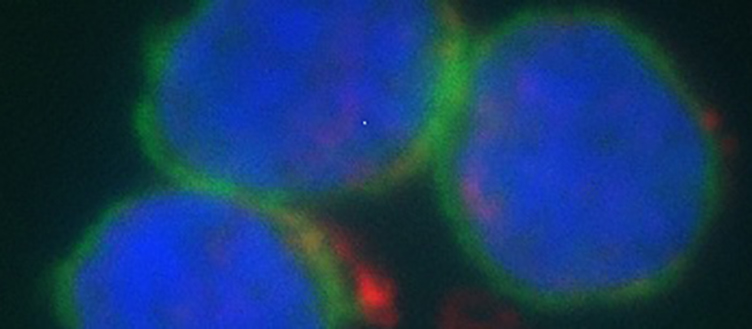

B lymphocytes (blue and green) and gold nanoparticles (red) measured with dark field hyperspectral imaging coupled with fluorescent detection. © UNIGE

Over the past twenty years, the use of nanoparticles in medicine has steadily increased. However, their safety and effect on the human immune system remains an important concern. By testing a variety of gold nanoparticles, researchers at the University of Geneva (UNIGE), in collaboration with the National Centre of Competence in Research “Bio-inspired Materials” and Swansea University Medical School, (United Kingdom), are providing first evidence of their impact upon human B lymphocytes – the immune cells responsible for antibody production. The use of these nanoparticles is expected to improve the efficacy of pharmaceutical products while limiting potential adverse effects. These results, published in the journal ACS Nano, will lead to the development of more targeted and better tolerated therapies, particularly in the field of oncology. The methodology developed makes it also possible to test the biocompatibility of any nanoparticle at an early stage in the development of a new nanodrug.

By following activation markers expressed on the surface of B cells, the scientists were able to determine how much their nanoparticles activated or inhibited the immune response. While none of the nanoparticles tested demonstrated adverse effects, their influence on the immune response differed depending on their shape and the presence of a surface, polymer coating. “Surface properties, as well as nanoparticle morphology definitely are important when it comes to the nanoparticle-cell interaction. Interestingly, the gold nanorods inhibited the immune response instead of activating it, probably by causing interference on the cell membrane, or because they are heavier”, says Martin Clift, an Associate Professor of Nanotoxicology and In Vitro Systems at Swansea University Medical School, and the project’s co-leader.